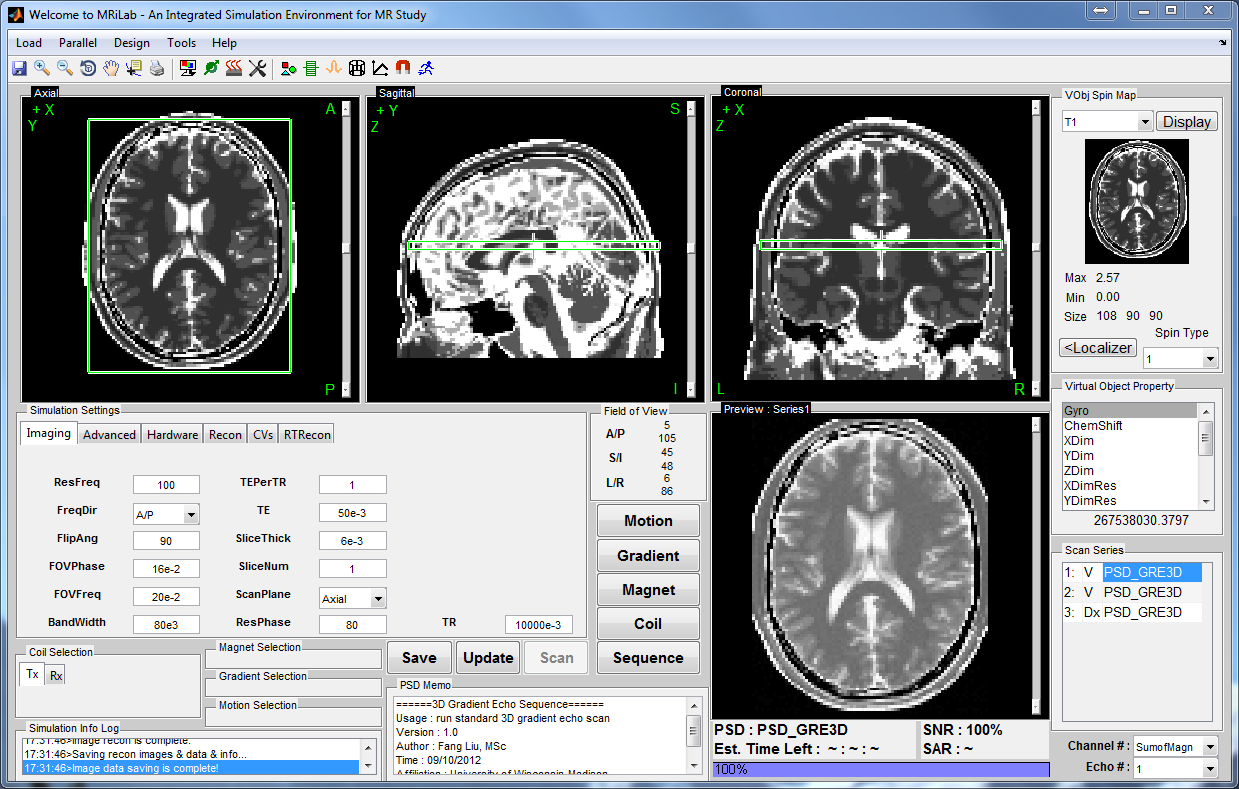

Processing Frameworks

visualization

segmentation

registration

analysis

data management

Matlab